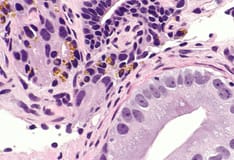

Adenocarcinoma of the prostate. Note the atypical hyperchromatic epithelium lining the glands and the pleomorphic nature of the malignant cells.